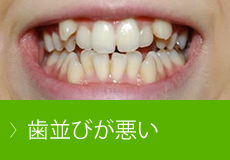

歯並びが悪い nセントラルクリニック歯科

歯並びが悪い とは 八千代台の豊歯科

キレイで良い歯並び 悪い歯並びの種類や原因 リスク 歯周病治療なら東京国際クリニック 歯科

綺麗な歯並びは財産になる 悪い歯並びの種類や原因を解明 おだデンタルクリニック